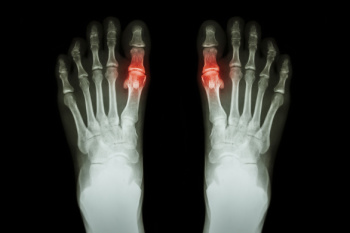

Morton’s Neuroma

Morton's neuroma is a painful foot condition that commonly affects the areas between the second and third or third and fourth toe, although other areas of the foot are also susceptible. Morton’s neuroma is caused by an inflamed nerve in the foot that is being squeezed and aggravated by surrounding bones.

Morton’s neuroma is a very treatable condition. Orthotics and shoe inserts can often be used to alleviate the pain on the forefront of the feet. In more severe cases, corticosteroids can also be prescribed. In order to figure out the best treatment for your neuroma, it’s recommended to seek the care of a podiatrist who can diagnose your condition and provide different treatment options.